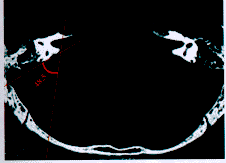

內耳平掃磁共振成像(MRI)是根據在強磁場中放射波和氫核的相互作用而獲得的。磁共振一問世,很快就成為在對許多疾病診斷方面有用的成像工具,包括骨骼肌肉系統。肌肉骨骼系統最適於做磁共振成像,因為它的組織密度對比範圍大。在骨、關節與軟組織病變的診斷方面,磁共振成像由於具有多於CT數倍的成像參數和高度的軟組織解析度,使其對軟組織的對比度明顯高於CT。磁共振成像通過它多向平面成像的功能,套用高分辨的毒面線圈可明顯提高各關節部位的成像質量,使神經、肌腱、韌帶、血管、軟骨等其他影像檢查所不能分辨的細微結果得以顯示。磁共振成像在骨關節系統的不足之處是,對於骨與軟組織病變定性診斷無特異性,成像速度慢,在檢查過程中。病人自主或不自主的活動可引起運動偽影,影響診斷。